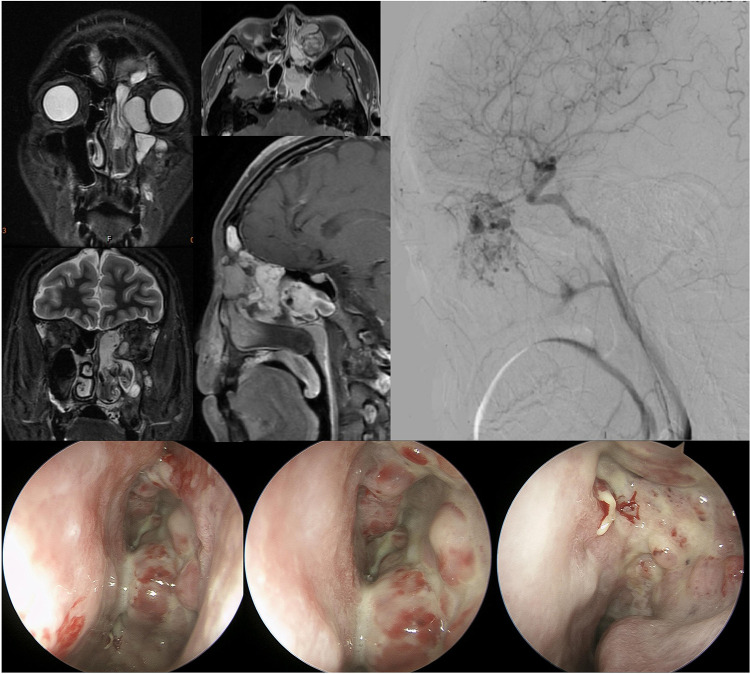

在本病例报告中,我们描述了一名左眼窝和鼻腔血管瘤反复发作的 21 岁男子。传统的手术并不成功,因此我们使用了贝伐单抗,一种抑制血管生长的药物。这种方法大大缩小了肿瘤的体积,并止住了频繁的鼻出血。两年多来,肿瘤一直得到控制,没有出现大的副作用,这表明贝伐单抗是治疗复发性血管瘤的一种很有前途的非手术疗法。

In this case report, we describe a 21-year-old man with recurrent hemangiomas in his left eye socket and nasal cavity. Traditional surgeries were unsuccessful, so we used Bevacizumab, a drug that inhibits blood vessel growth. This approach significantly reduced the tumor size and stopped frequent nosebleeds. Over two years, the tumor remained controlled without major side effects, suggesting Bevacizumab as a promising non-surgical treatment for recurrent hemangiomas.